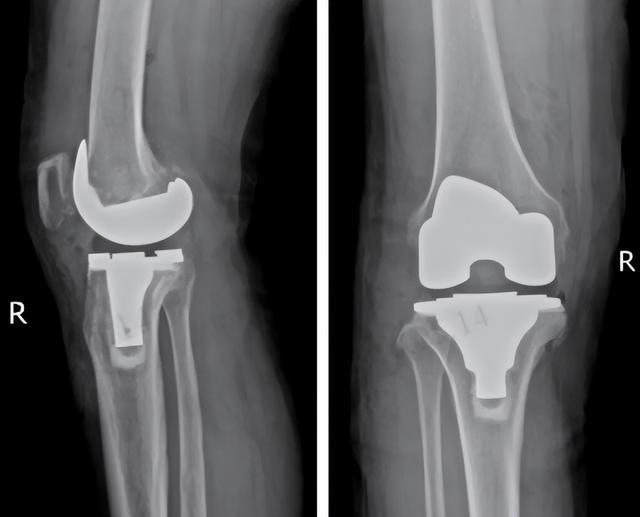

(▲术后膝关节影像片,内侧关节间隙恢复正常)

在医护精心照料下,术后第二天尹阿姨就能下地行走!纠缠许久的剧痛明显缓解,僵硬的关节重获灵活,久违的笑容又回到了她脸上。

当膝关节病变严重时,需做“膝关节置换”。很多人一听“膝关节置换”就害怕,其实大可不必。手术并非换掉整个关节,只是修整磨损的软骨和薄层病变骨面,再植入人工关节面,相当于给膝盖镶上一层“保护壳”。这样既能极大缓解疼痛、矫正变形,又能保留患者自身的大部分骨骼和韧带,术后关节更稳定、功能恢复也更快。